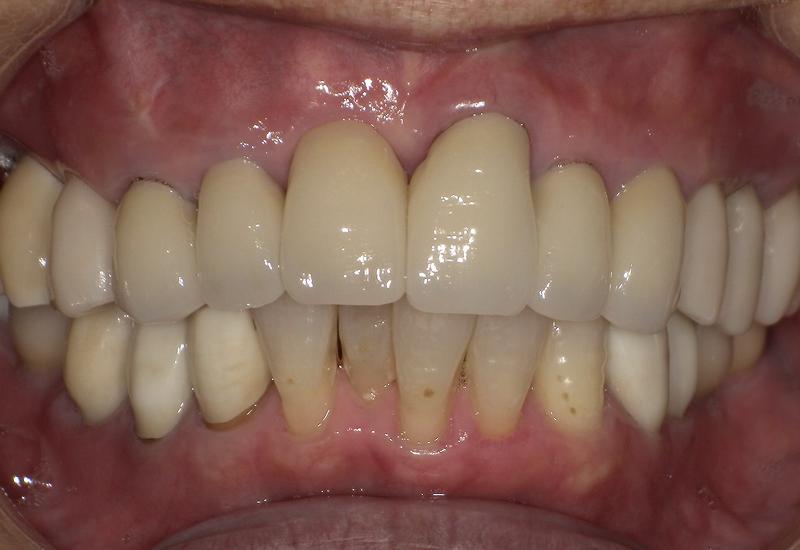

症例① シェイプメモリーアライナーによる下顎の前歯の矯正

治療期間 7ヶ月

治療時の年齢/性別 68歳 / 女性

かかった治療費 440,000円

治療方法 シェイプメモリーアライナー

注意点・詳細

• 根管治療をしてある歯はなるべく動かさない

• 下の前歯の歯の形を少しだけ小さく整えた